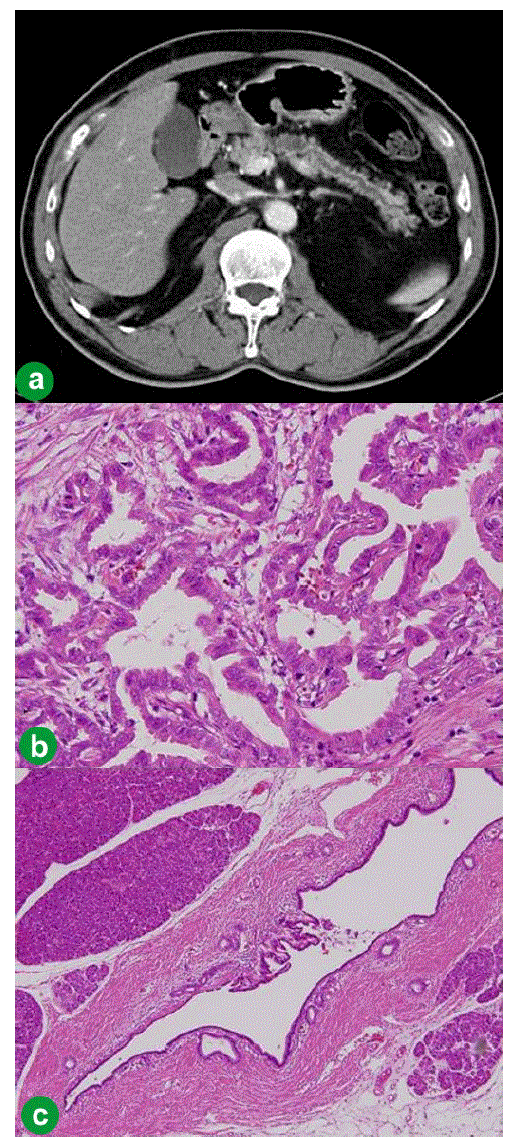

Based on this image's title: “Figure 2 from Duodeno-Pancreatic Preservation in a Big Tumor of the ...”